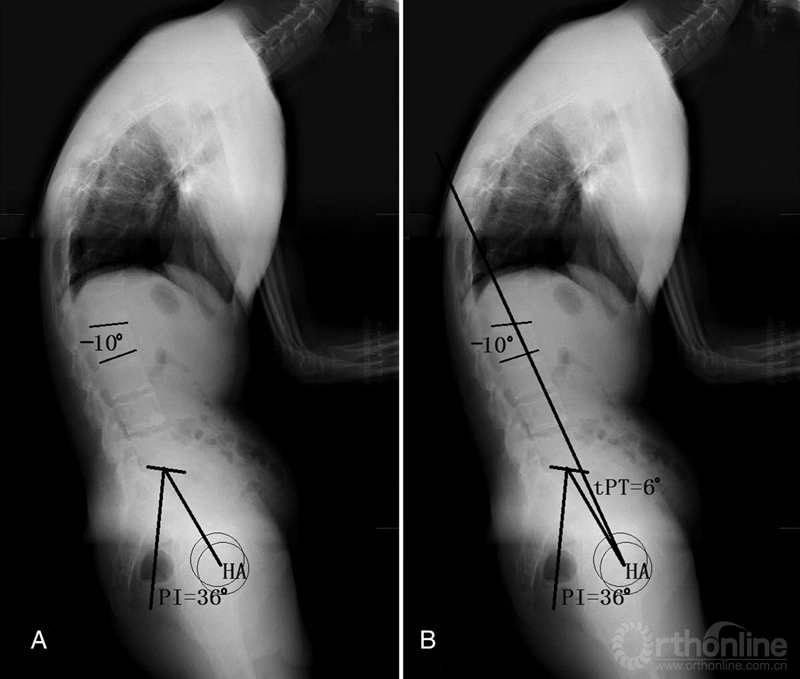

图5 单节段截骨角度的确定步骤和方法 A 测量患者PI值并确定要进行截骨的节段; B 计算理论PT(tPT)值=0.37×PI-7°,画出tPT线; C 以截骨节段旋转中心(PSO为椎体前缘中点)为圆心RP,到肺门HP线段为半径画圆,与tPT线相交点HP′,∠HP-RP-HP′角度为截骨角度; D最终矫形后tPT线垂直,且tPT线通过人体重心(肺门HP)

(图片资料摘自Song等A New Method for Calculating the Exact Angle Required for Spinal Osteotomy, Spine (Phila Pa 1976), 2013, 38(10):E616-20.)